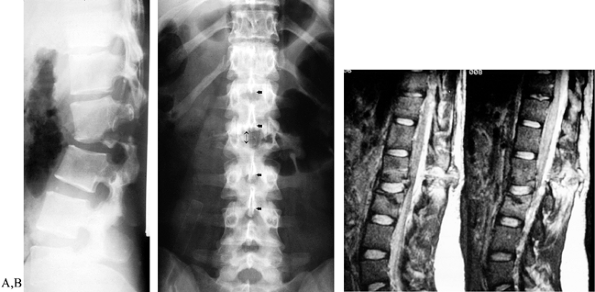

Figure 141.8. Radiographic characteristics of burst fractures. A:

Lateral view demonstrates fracture of anterior cortex and superior endplate, with resulting focal kyphosis. The posterosuperior portion of the vertebral body can be seen retropulsed into the spinal canal, with loss of normal concave contour of the posterior vertebral body. B: AP radiograph demonstrates the increased intrapedicular distance associated with a burst fracture; the distance between the L-1 pedicles is significantly greater than for the levels either above or below, indicating a complete disruption of anterior, middle, and posterior columns. |

the spinous processes and the disruption of the pedicle in most cases (Fig. 141.9)

Figure 141.9. Radiographic characteristics of seat-belt fractures. A:

Lateral radiograph of severe flexion–distraction injury, taken in sitting position. The patient was admitted following a head-on motor vehicle accident and treated for abdominal contusions, splenic rupture, and rupture of the colon. Injury was not apparent on supine radiographs. B: AP radiograph shows wide spacing between spinous processes at the level of injury. C: MRI confirms extensive soft-tissue disruption including rupture of the lumbodorsal fascia. |